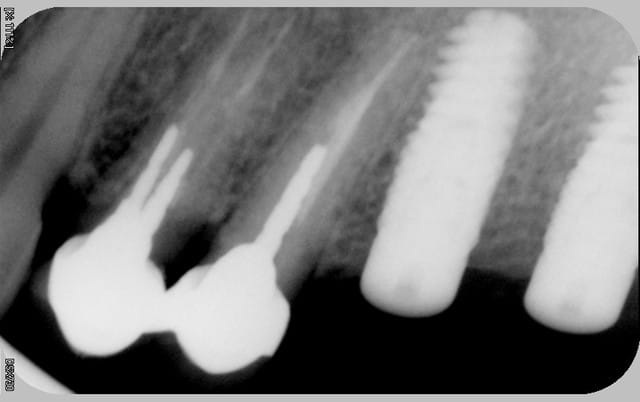

tous mes implants sont ostéo-intégrés, mais je trouve que la cratérisation est très importante et surtout très rapide.

donc pour moi, il y a un problème même si le taux de succès est de 100% en 2 ans.

Il manque les radios du jour de la pose, j'ai l'impression que les implants ne sont pas assez enfouis . Pa exemple Anthogyr recommande de poser l'Axiom 0.5mm en sous crestal, que préconise Tekka ?

En ce qui concerne la radio de la 21 , on dirait qu'il a été mis dans un site d'extraction et qu'il n'est pas assez large.

voici les radios le jour de la pose

le krestal doit être en crestal et non en infra-osseux: il s'agit d'une connectique à plat et non d'un cône morse.

il me semble que sur le 1° cas présenté,la partie biseautée de l'implant est enfouie et que la cratérisation est nulle, idem pour l'implant mésial du dernier cas.

Sur son site Tekka préconise de mettre la partie supérieur de l'implant en juxtacrestal , donc le biseau est infraosseux...

J'avais rencontré le même pb sur un cas que j'avais présenté sur ce forum sur des IDcam et l'on m'avait fait remarqué à raison que l'enfouissement de l'implant distal était insuffisant, résultat a 6 mois cratérisation mésial et distal du dernier implant et à un an stabilisation .

Tu remarqueras que le biseau mésial de l'implant mésial qui a été correctement enfoui n'a pas bronché.